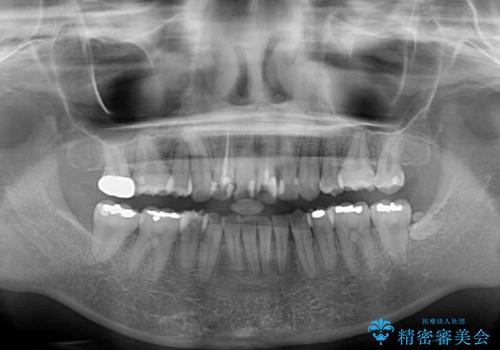

- 内側に倒れ込んだ歯や下の前歯が隠れてしまうほどの咬み合わせを改善したいとのことで来院された患者様です。

下顎の叢生を解消するために抜歯が必要であり、奥歯の咬み合わせや口元の印象から、上顎も同様に抜歯と判断し、上下左右の第1小臼歯4本抜歯してワイヤー装置にて矯正治療を行うこととしました。

咬み合わせが深く、そのままでは上顎の抜歯スペースが閉じきらない可能性があったため、治療初期から深い咬み合わせを改善させるように試みました。

実際にはなかなか改善されず、当初予定よりも治療期間がやや長期化してしまいました。